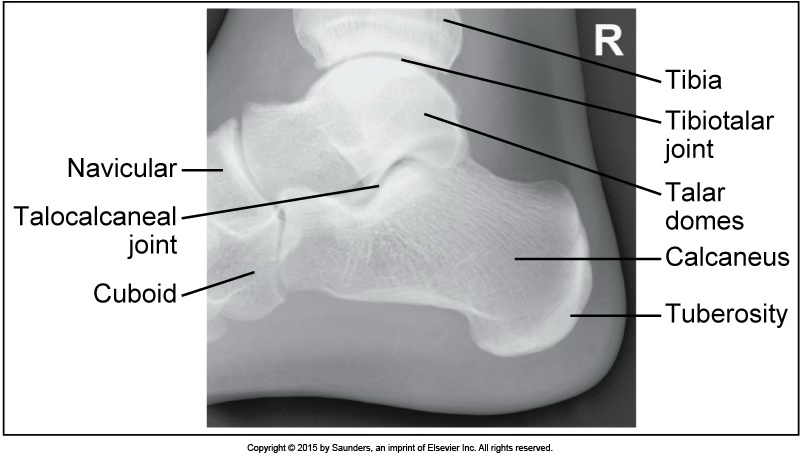

medialateral foot

accurate positioning